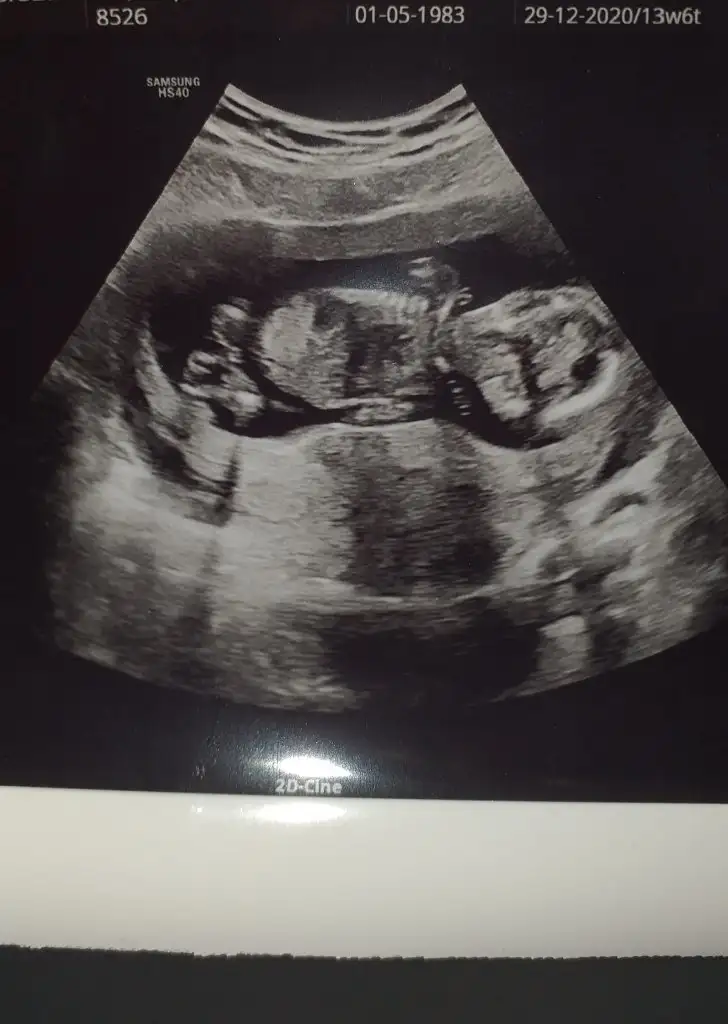

Kızlarr selam bende cinsiyet tahmini alabilir miyim😍

Eklentiler

• 91B2775E-DAD5-468E-9AA1-CF97C6A6E882.webp

91B2775E-DAD5-468E-9AA1-CF97C6A6E882.webp

31,5 KB · Görüntüleme: 53